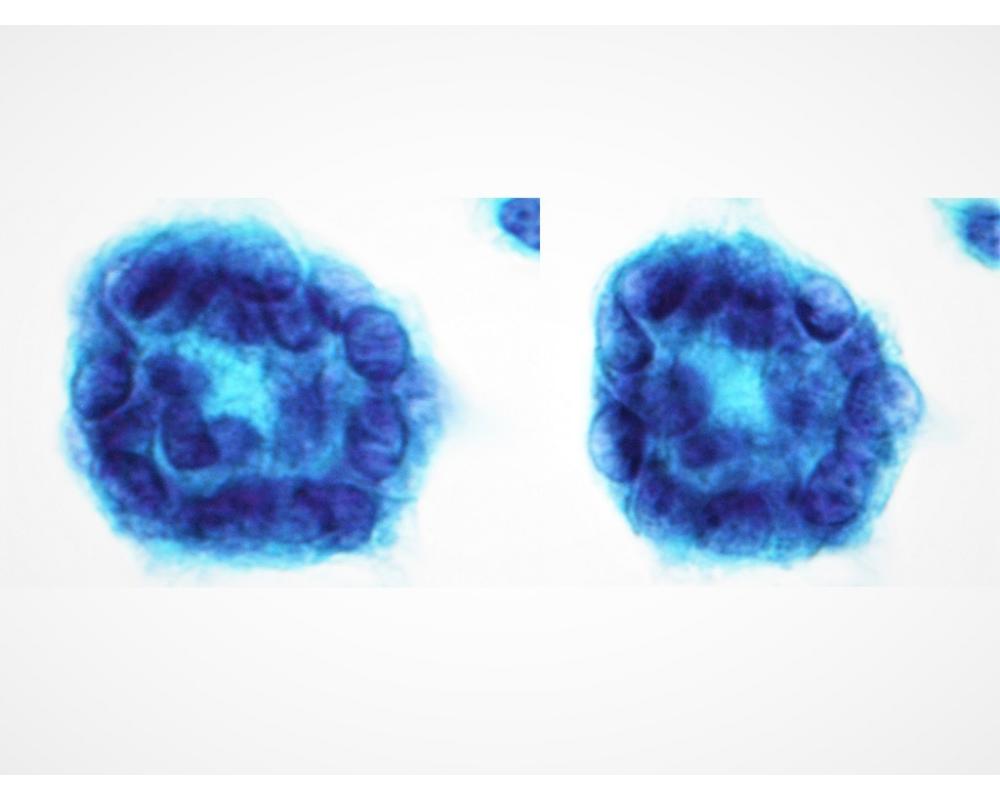

第38回日本臨床細胞学会九州連合会学会(熊本)スライドカンファレンス症例4

種別:泌尿器

出題:石原 明 潤和会記念病院病理診断科

| 年齢 | 70代 | 性別 | 男性 |

| 採取部位 | 尿 | 採取方法 | 自然尿 |

| 検体処理法 | LBC法(サイトリッチレッド、BD SurePath) |

既往歴:高血圧、心房細動、左鼠径ヘルニア手術。

現病歴:10ヶ月前 肉眼的血尿(主訴)、4ヶ月前 近医受診し、PSA値24.5、膀胱鏡にて前立腺部尿道の乳頭状

腫瘍指摘、当院紹介受診。

画像診断では左外鼠径・内外腸骨・総腸骨各リンパ節腫大。

臨床診断:前立腺癌・転移あり、尿道部尿路上皮癌。

| 正解 | 4. 前立腺導管型腺癌 |

▼選択肢及び投票結果

| 1.扁平上皮癌 | 0件 | (0.0%) | |

| 2. 尿路上皮癌 HGUC | 17件 | (16.3%) | |

| 3. 神経内分泌癌 | 0件 | (0.0%) | |

| 4. 前立腺導管型腺癌 | 84件 | (80.8%) | |

| 5. 前立腺尿道ポリープ | 3件 | (2.9%) | |

| 投票総数 | 104件 | (100%) |